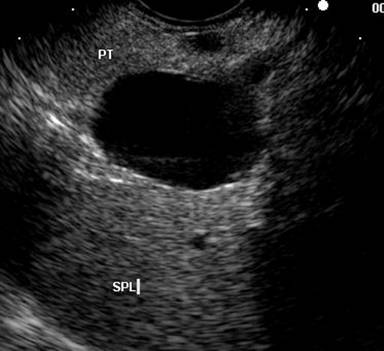

A 45-year-old female was referred for evaluation of an incidental cystic lesion in the tail of the pancreas (Figure 1). Initial EUS examination revealed a 29x18 mm unilocular cyst in the tail of the pancreas (Figure 2). EUS-FNA yielded a clear watery fluid with a CEA level of 7.4 ng/mL and an elevated amylase level of 158,464 IU/L. Cytology revealed rare macrophages with debris; a mucicarmine stain was negative. The results were felt to be most consistent with a pseudocyst; however, there was no history of pancreatitis. Surveillance EUS was recommended and was performed one year later. This exam revealed a 36x30 mm anechoic cyst with a very small septation. The cyst aspirate was clear but slightly viscous, with an elevated CEA level of 457 ng/mL. Cytology again revealed macrophages and degenerated cells with a negative mucicarmine stain. A mucinous cystic neoplasm was suspected, and the patient underwent uneventful laparoscopic resection. Final surgical pathology revealed a mucinous cystic neoplasm with focal borderline features (Figure 3).

Figure 2. Initial EUS revealing a 29 mm cyst in the pancreatic tail. (Patient #1). PT: pancreatic tail; SPL: spleen |